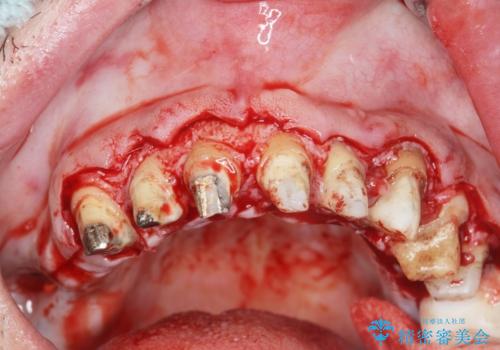

歯周外科を行い歯と歯槽骨・歯肉の関係を是正することで歯ぐきの状態を改善し、将来に亘り安定した歯周環境の維持を期待できるセラミック治療を実践します。

歯ぐきが腫れたままの状態だと、違和感が生じるとともに常に炎症が存在する環境となってしまうので非常に好ましくない口腔内環境です。

- 外科手術のため、術後に出血、痛みや腫れ、違和感を伴います